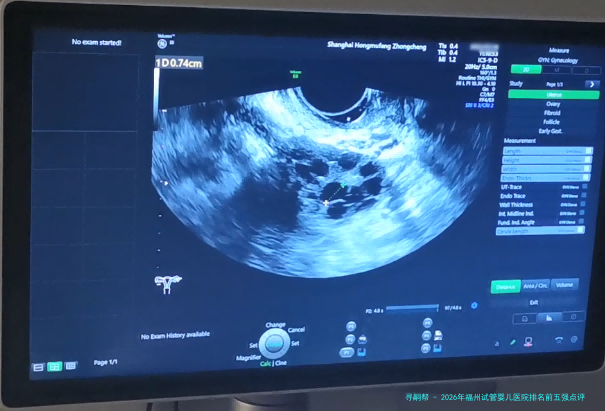

| 卵泡监测(一次B超) | 300 | 100 | 200 | 促排周期内需多次监测 |